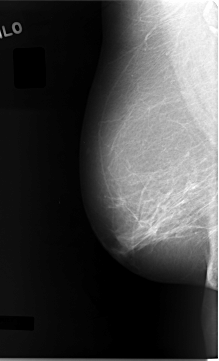

C_0027_1.LEFT_MLO

LEFT_MLO LINES 5824 PIXELS_PER_LINE 3656 BITS_PER_PIXEL 12 RESOLUTION 50 OVERLAY